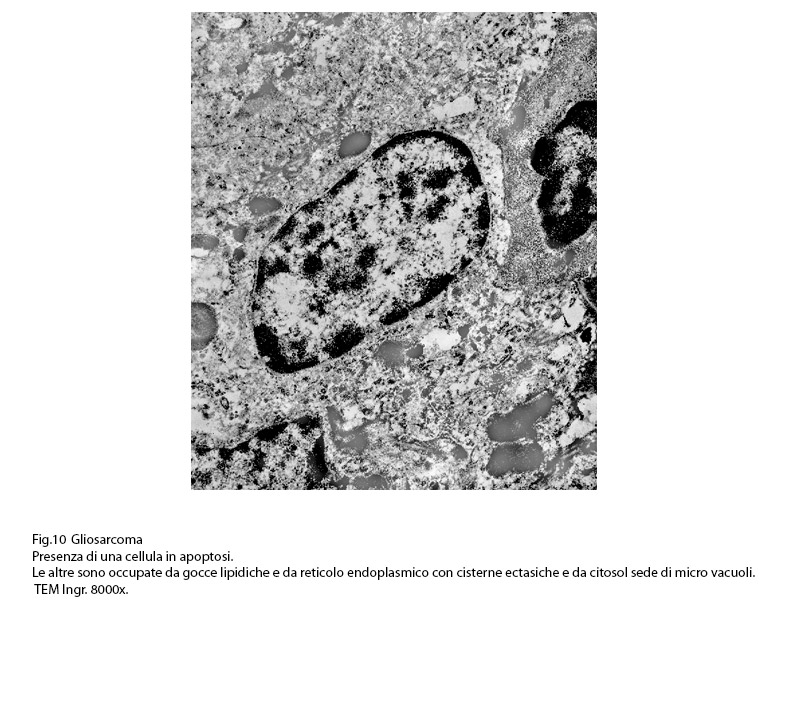

Come è già ampiamente documentato, i lisosomi sono determinanti nei processi di apoptosi, di autofagia e di necrosi; a tali eventi è necessario aggiungere anche la esistenza della morte cellulare lisosomiale indotta da enzimi lisosomiali riversati nel citosol. (FEBS J, 2015; 282: 4279-4288).

Nelle cellule di gliosarcoma qui esaminate si repertano con scarsa frequenza lisosomi primari o secondari;i primi appaiono come corpi densi,compatti, elettropachi,immersi nel citosol ;i secondi si presentano quali strutture cave delimitate da una membrana a monostrato.

Nel citoplasma delle cellule di gliosarcoma esaminate sono stati riscontrati con frequenza focolai di autofagosomi e di autolisosomi; i primi si riconoscono quali corpi ovoidali o rotondeggianti i quali sono demarcati da una membrana a doppio contorno e contengono nel loro spazio cavo materiale granuloso,filamentoso ed amorfo; i secondi,gli autolisosomi, sono delimitati da una membrana a monostrato,spesso notevolmente ispessita per sovrapposizione di materiale amorfo;il loro contenuto è rappresentato da materiale biologico in varie fasi di degradazione.

Frequentemente sono sti riscontrate nell’ambito della stessa cellula la coesistenza di alterazioni diverse e allo stesso modo è abituale il riscontro di elementi cellulari tra loro coesi,dei quali uno si trova in uno stato di necrosi apoptotica,gli altri sono in uno stato di necrosi post-vacuolizzazione lisosomiale.

Fig.9  Fig.10

Fig.10